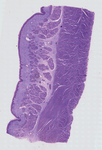

Dog Esophagus

The esophagus (or oesophagus; see spelling differences), sometimes known as the Gullet, is an organ in vertebrates which consists of a muscular tube through which food passes from the pharynx to the stomach. During swallowing food passes from the mouth through the pharynx into the esophagus and travels via peristalsis to the stomach.